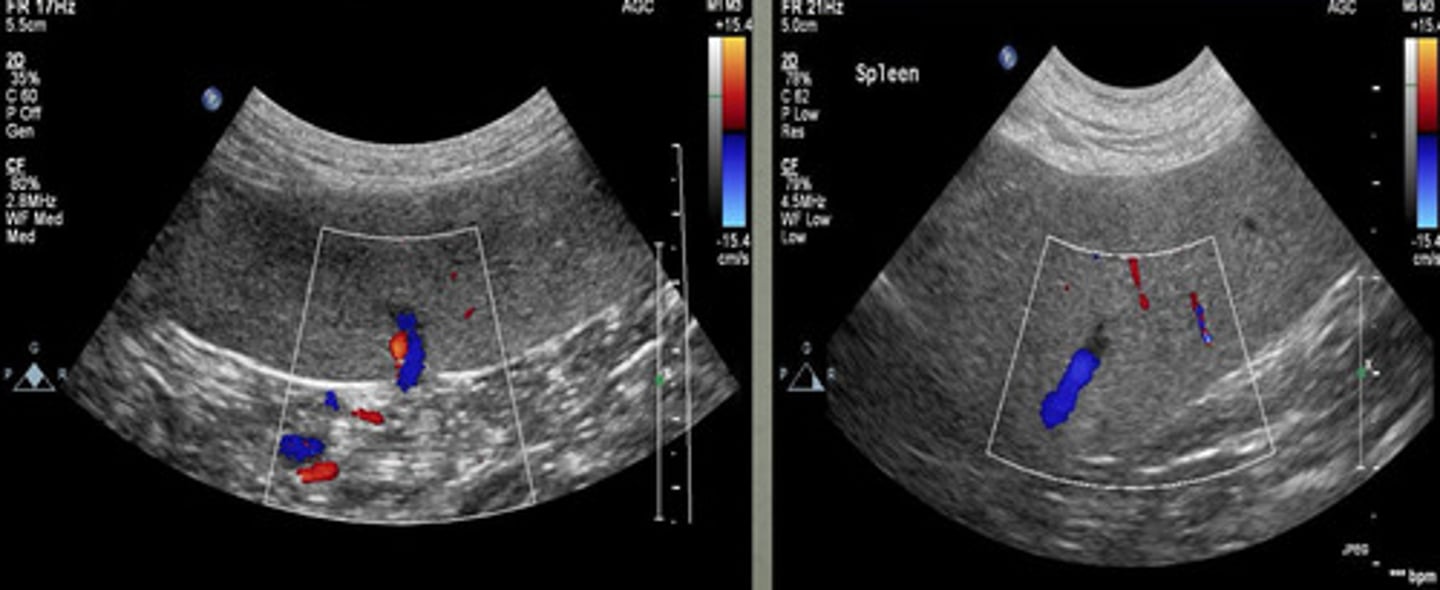

color dopler

what type of tool is being used in this ultrasound to see the different vessels?